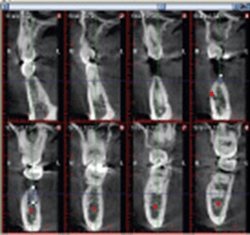

上記写真は、CT撮影後、インプラント埋入予定の理想の部分がどこなのかを診断し、CT上でインプラントを埋入した写真です。黄色の線は神経が通っている部分になりここにインプラントが入ってしまうと麻痺などが起こってしまいます。神経を避けて埋入できます。

骨の密度を確認することが可能

①の写真を密度のわかる写真にしたものが②の写真になります。赤い部分が骨がかたい部分になります。③の写真はインプラント予定部分の断面図です。

中央の緑と青の部分は骨がやややわらかいのですが、そのまわりはしっかり赤くなっていて骨が硬いのがわかりますので、この部分には太めのインプラントを埋入することにより硬い骨の部分にしっかりくっつくようになり安定するのです。